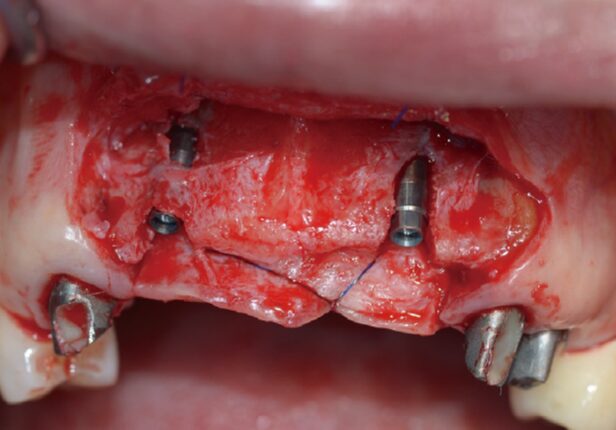

Colocação do implante

Posicionamento AXA